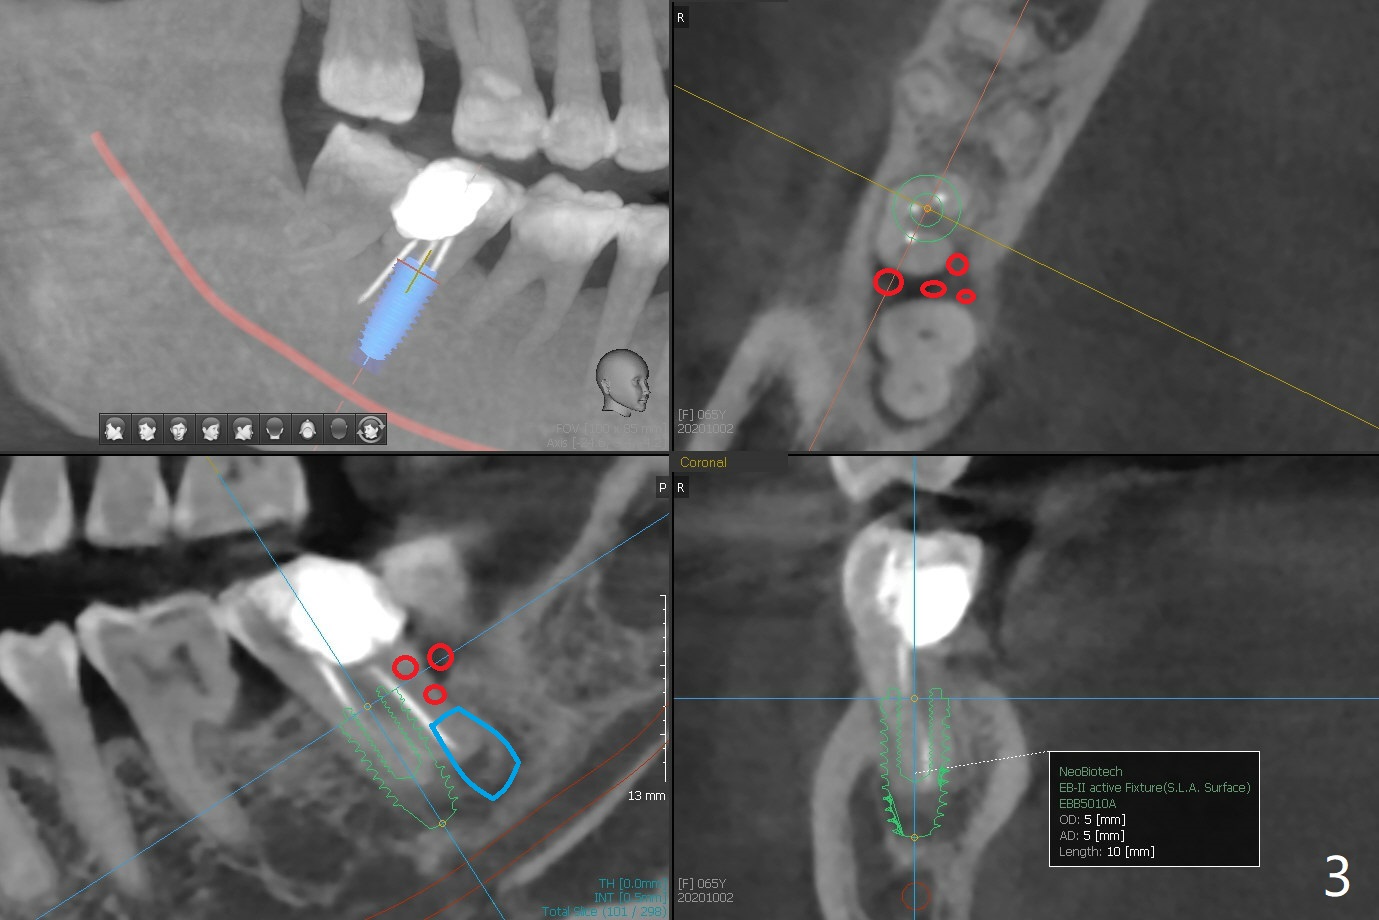

65岁女右下7远中舌侧龈下龋坏(图一,二),远中骨质吸收严重,植体应植入近中窝(图三:绿色),远中窝根部放置胶原塞(蓝色),冠部粘性骨粉(红色)。洁治邻牙,智齿近中面涂Endogain。